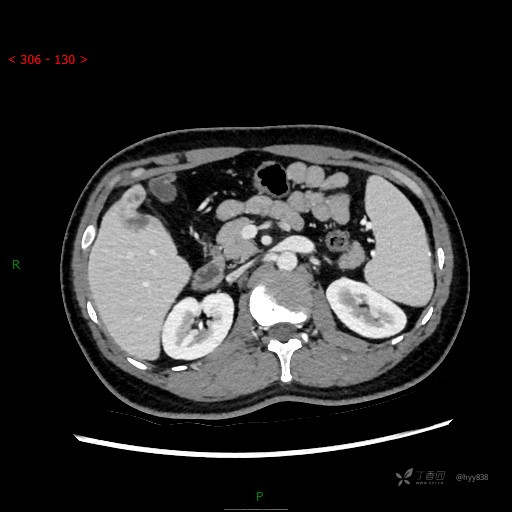

延迟期